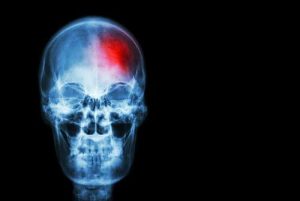

عندما لا يتدفق الدم جيدا إلى الدماغ، لا تحصل الخلايا على العناصر الغذائية والأكسجين التي تحتاج إليه، ولذلك تموت.

توجد أنواع مختلفة من السكتة الدماغية. وهو الأمر الذي يعتمد على المنطقة المتأثرة في الدماغ.

السكتة الدماغية الإقفارية

هذا النوع من السكتات الدماغية يطلق عليه اسم الهجوم الانسدادي أو الانتهاك الدماغي ويحدث عندما يتم فقدان إمداد الدم إلى المخ بصورة مفاجئة.

يحدث هذا بسبب انسداد شرايين معينة مسؤولة عن إمداد الدم إلى الدماغ بسبب تراكم الكالسيوم أو الانسداد الدموي أو تصلب الشرايين.

السكتة الدماغية النزيفية

هذا النوع من السكتات الدماغية يحدث عندما تتمزق أوعية الدم في الدماغ، سواء بسبب أم الدم الخلقية أو ارتفاع ضغط الدم.

هذا النزيف يسبب سكتة دماغية لأنه يحرم منطقة الدماغ من إمداد الدم أو لأن الدم يضغط على هيكل الدماغ.